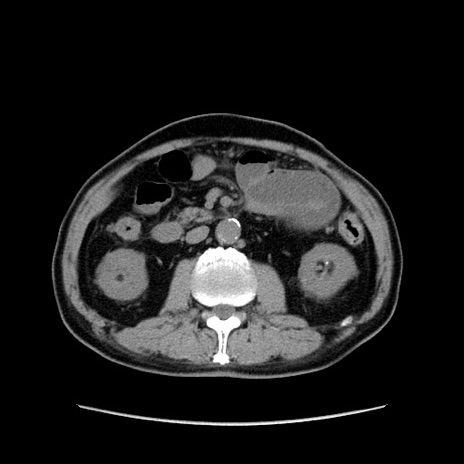

症例24(横断像)

【症例】80歳代男性

【主訴】左側腹部痛、嘔吐

【現病歴】本日早朝より左腹部に痛みあり。昼頃嘔吐認めたため、救急要請。

【既往歴】直腸癌(Mile手術)、胆摘

【身体所見】意識清明、BT 35.9℃、BP 221/93mmHg、SpO2 97%(RA) 、腹部:左ストーマ周囲に限局性の腹部膨隆あり。 膨隆部自発痛・圧痛あり・軟。

【データ】WBC 7700、CRP 0.09